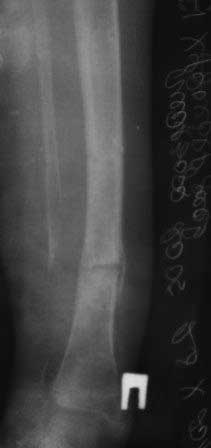

Уважаемые коллеги.Очень прощу помочь в одном сложном деле. Девочка 2005г.р. В середине 2008 г падает с велосипеда с дедом, возможно был перелом н/з костей левой голени, лечение у знахаря-табиба, но ребенок не смог бегать, часто падал, начал хромать. Май 2009г. обратились к нам, установлен д-з « вялоконсолидирующаяся перелом н/з б/берцовой кости, несросшийся перелом м/берцовой кости со смещением по ширине». Мы решили гипсовая повязка и ходьба с нагрузкой, но по категорическому требованию родителей исправить деформацию м/берцовой кости, произвели операцию ( на свою голову )»о/ репозиция и и/м фиксация спицами м/берцовой кости». Теперь началась самая интересная история! Ч-з недели две в обл. п/о раны м/берцовой открылась свищ с кровянистым выделением, гноя не было, на р-грамме лизис концов отломков м/берцовой кости, к-рый начал прогрессировать, консультирована онкологами, цитология, с подозрением направлена в центральные институты, сделана КТ, онкологическое исключили, в августе попали в остеомиелитический центр, где произведена резекция м/б на протяжение 6-7см, все зажило и выписали (снимок-1). 2010г в мае повторно получила травму, наложена гипсовая повязка (снимок-2) и через 1-2 месяца в одном из центральном институте произведена КДО аппаратом Илизарова , который снят ч-з три месяца (снимок-3) и долго ходила на костылях-мать заставила, как начала наступать, появилась деформация, заказали ортез и так ходила, но деформация прогрессировала, Обратилась к нам в апреле 2012г,(снимок-4) произведена постепенная коррекция на аппарате, и замена на БИОС 01.03.12г плечевым гвоздем, ЭОП нет, поэтому осталась несколько антекурвация (снимок-5), ребенок ч-з неделю начала ходить.Повторный осмотр 22.06.12г- деформация усиливается, за три месяца сращение очень слабое.(снимок-6). (Жаль что многие р-снимки не сохранились, мать обещала хотя бы часть найти)!Что теперь делать? Удалить дистальные винты и пробовать исправить на аппарате, или гвоздь убрать , коррекция на аппарате и после рассверливания повторный БИОС? Уважаемые коллеги, какие варианты предлагаете? С уважением Абдурашид.